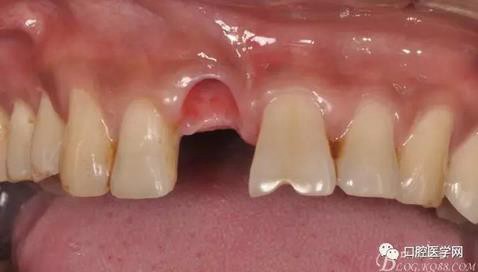

圖4 術(shù)前正位頜面照

圖5 拔除殘根

圖6 術(shù)中植入植體